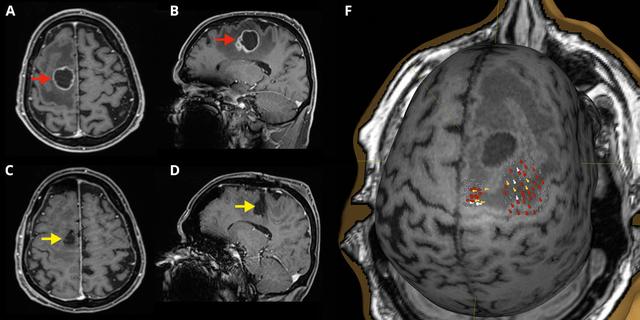

3. Diagnoseverfahren

Zur Diagnose von Hirnmetastasen werden verschiedene Untersuchungsverfahren eingesetzt:

– Neurologische Untersuchungen zur Überprüfung von Hirndruck und Gehirnfunktionen

– Bildgebende Verfahren wie Magnetresonanztomographie (MRT), Computertomographie (CT) und Positronenemissionstomographie (PET)

– Gewebeproben aus einer Biopsie zur weiteren Analyse